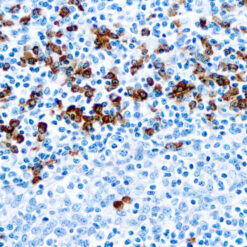

Calponin-1

Multiple isoelectric variants of calponin have been identified but only two molecular weight isoforms exist (34kDa and 29kDa). Expression of the 29kDa form, I-calponin, is primarily restricted to muscle of the urogenital tract, whereas the higher molecular weight variant has been demonstrated in vascular and visceral smooth muscle. Calponin is a calmodulin, F-actin and tropomyosin binding protein, which is thought to be involved in the regulation of smooth muscle contraction. Calponin expression is restricted to smooth muscle cells and has been shown to be a marker of the differentiated (contractile) phenotype of developing smooth muscle.

| Positive Control Tissue | Uterus |